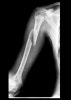

AP & lateral X-ray로 확진이 가능합니다.

X-ray 검사 시에는 어깨와 팔꿈치를 다 포함해야 합니다.

X-ray : 상완골 간부 골절(Humeral shaft fracture)